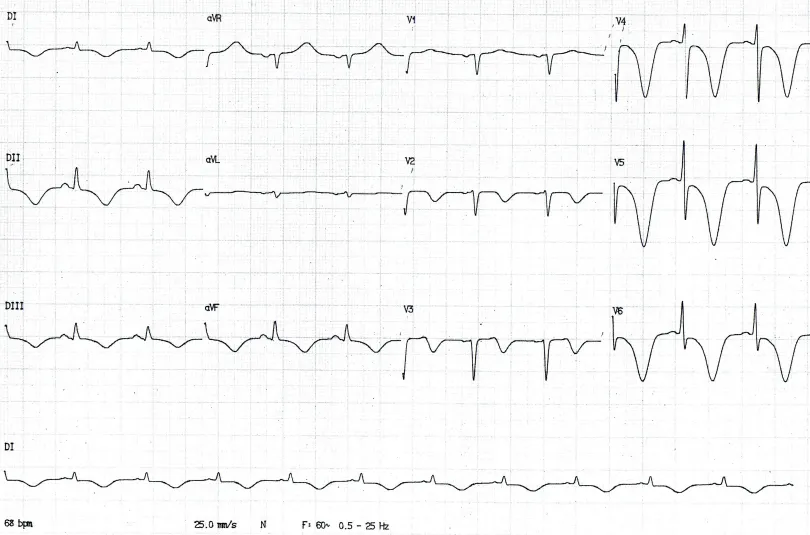

A presença de onda T apiculada, positiva e simétrica ou inversão de onda T associado a uma história de precordialgia pode sugerir isquemia miocárdica, como no exemplo abaixo.

Paciente com infarto sem supra de ST: